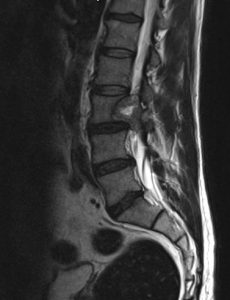

Paciente de 52 años que refiere lumbalgia inespecífica con irradiación ocasional en muslo (justo arriba de la rodilla) derecha. Sin focalidad.

Imagen con gadolinio, distribución homogénea, bordes definidos; la resolución ósea no significa malignidad en estos tumores; la ocupación de canal >50% tampoco significa que sean intradurales subaracnoideos